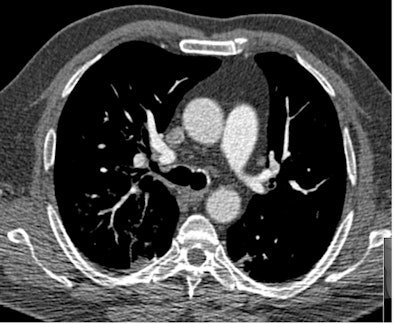

| All three CT images are from the same female patient weighing 95 kg with no pulmonary emboli. Above are two coronal maximum intensity projection (MIP) images, and below is a 1-mm thin transverse slice. At this body weight, 80-kVp CT angiography protocols provided good image quality and a high enough diagnostic confidence to exclude pulmonary embolism. All images courtesy of Dr. Zsolt Szücs-Farkas. |